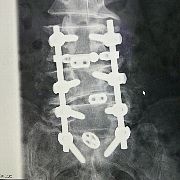

| 左側面 | 正面 |